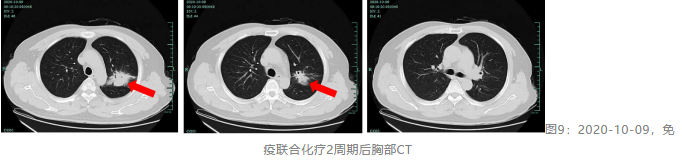

鳞状非小细胞肺癌(NSCLC)患者由于很少有驱动基因的改变,靶向药物疗效有限。随着肿瘤免疫治疗的发展,免疫检查点抑制剂在鳞状NSCLC中的应用潜力逐渐显现。替雷利...

肺癌是全球发病率和死亡率最高的恶性肿瘤,而作为非小细胞肺癌(NSCLC)常见的组织学类型之一,晚期肺鳞癌的治疗仍面临很大的挑战。近年来新的治疗策略如靶向治疗和免疫...